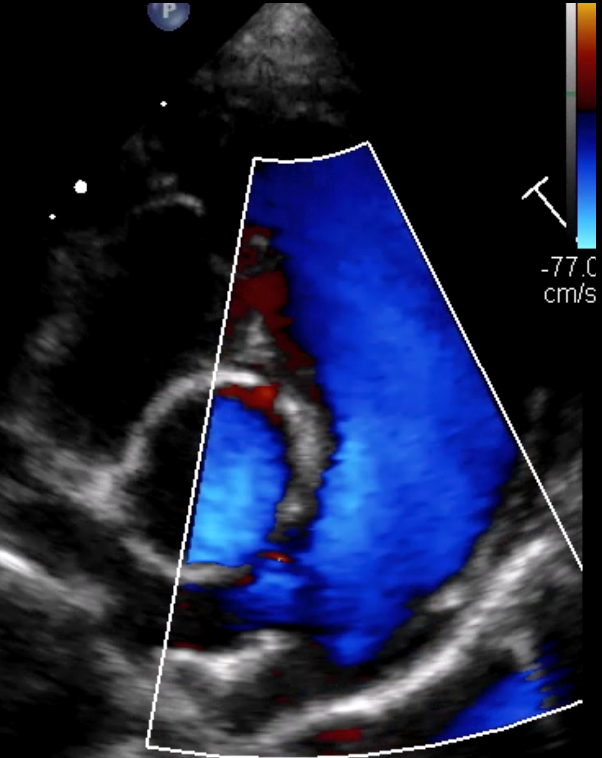

• Identifier, classifier et graduer les cardiopathies congénitales à partir des anomalies détectées en échocardiographie 2D, TM et Doppler.

• Interpréter de manière croisée les informations issues des différents modes échographiques (2D, TM, Doppler) pour affiner le diagnostic.

Analyse de cas cliniques illustrés par des images fixes et/ou des vidéos d’échocardiographie (2D, TM, Doppler).

Objectif : apprendre à repérer, décrire et interpréter les anomalies échographiques dans une démarche diagnostique rigoureuse, jusqu’à l’établissement de diagnostics différentiels.

Revue des bases en échocardiographie 2D, TM et Doppler appliquées aux cardiopathies congénitales.